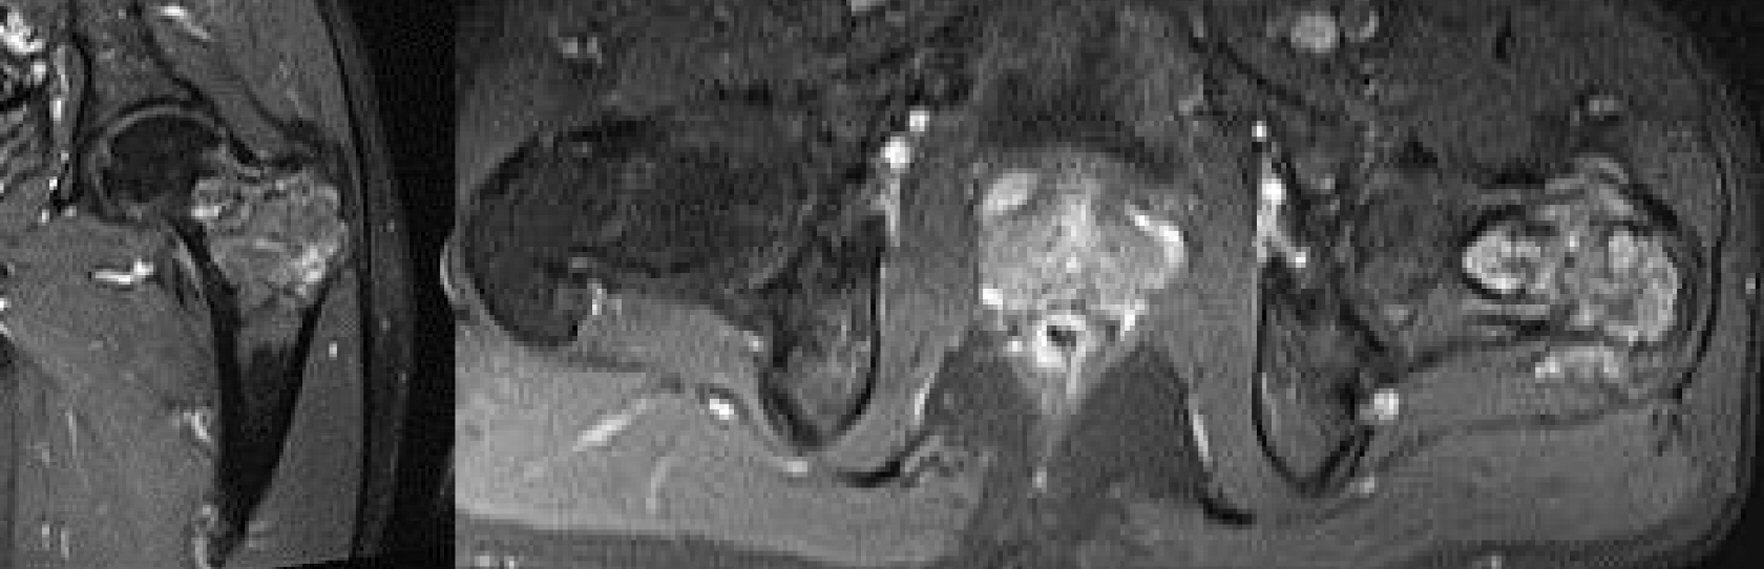

Magnetic resonance imaging (MRI) examination was carried out to further examine this intramedullary mass. There was an intramedullary heterogeneous cystic mass appearance in the proximal part of the left femur (Fig. 2). The posterior cortex was destroyed and there was soft tissue extension resembling aneurysmal bone cyst, and Jamshidi needle biopsy was advised.

![]() Click for large image | Figure 2. Preoperative MRI view. MRI: magnetic resonance imaging. |